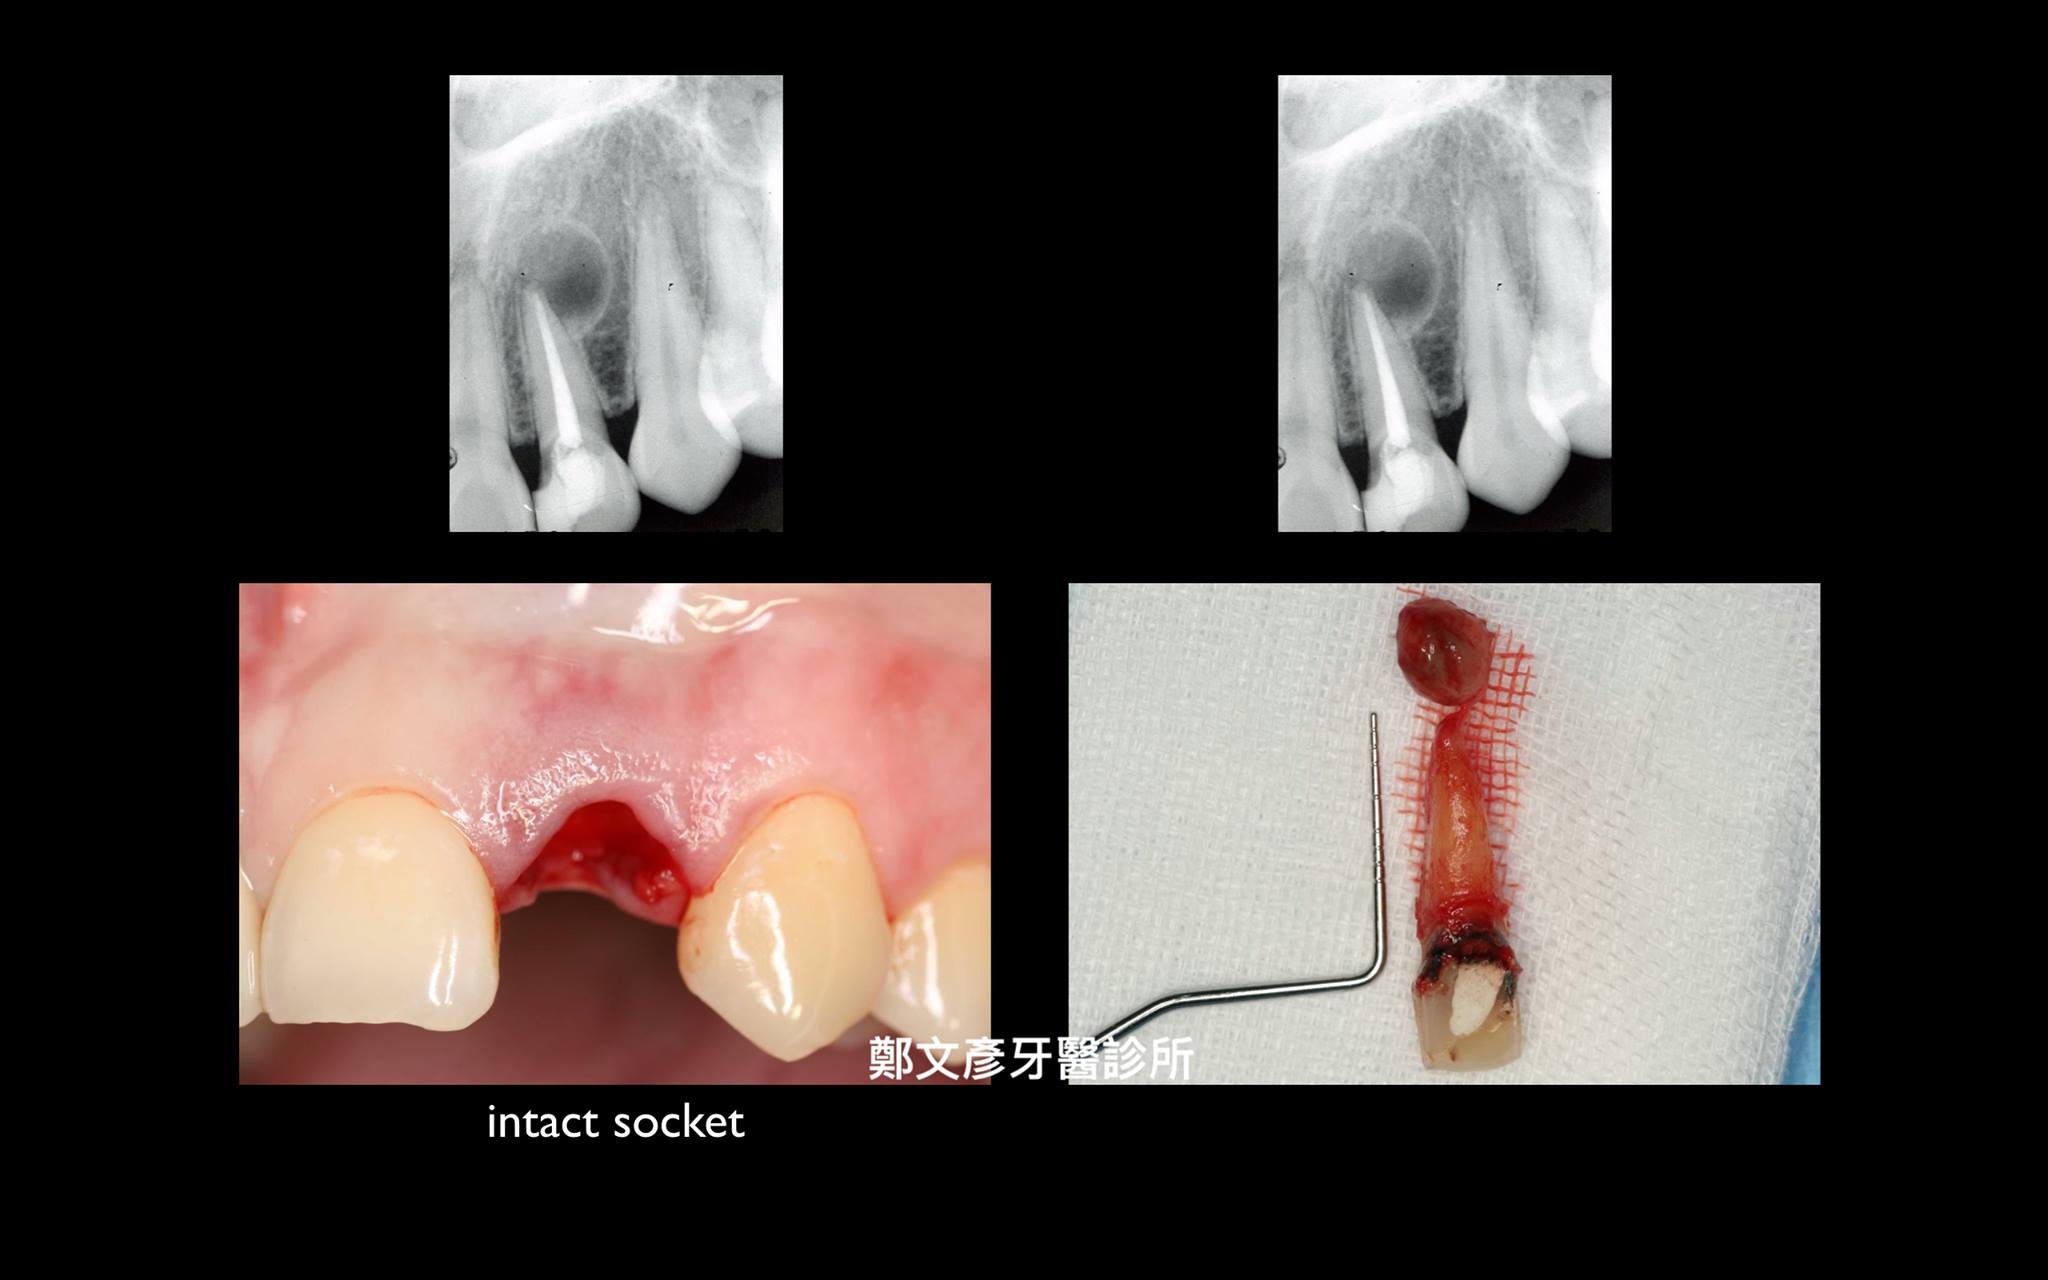

前牙植牙美學及軟組織轉移

植牙美學

植牙美學(後牙區)